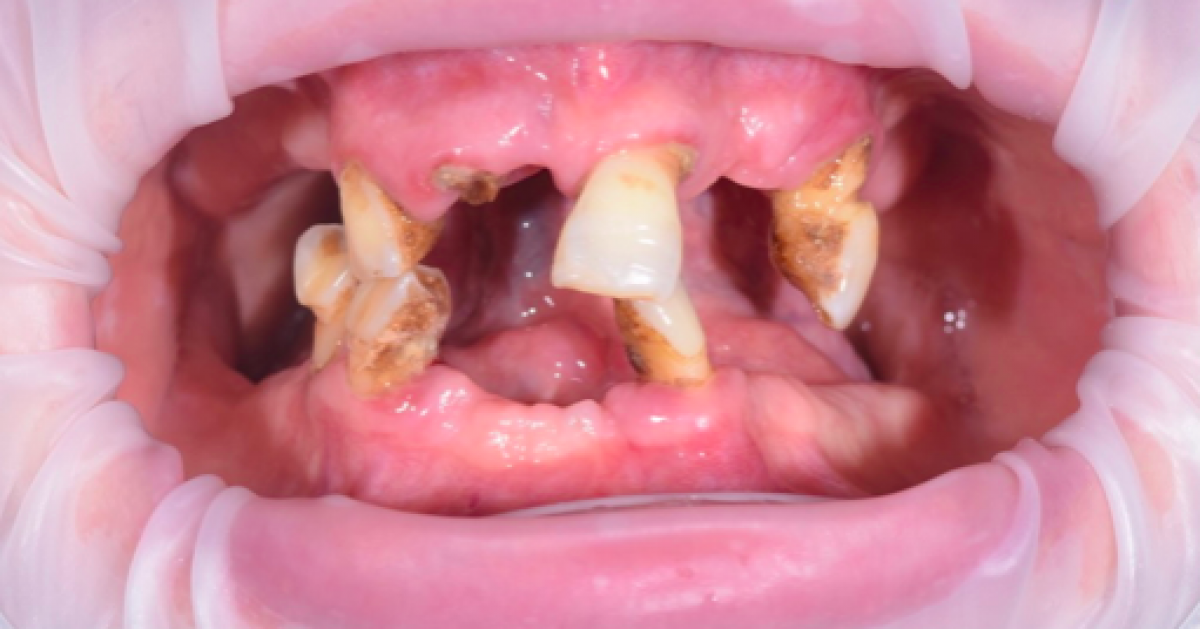

A 63-year-old female patient, smoker, in good general health, with severely compromised dental arches.

X-ray examination with orthopantomography showed severe periodontal disease in the few remaining teeth in the arches and significant bone resorption in the maxilla, resulting in a severe loss of vertical dimension. Cone Beam CT is required in order to establish a proper treatment plan. (PICTURE 1,2)